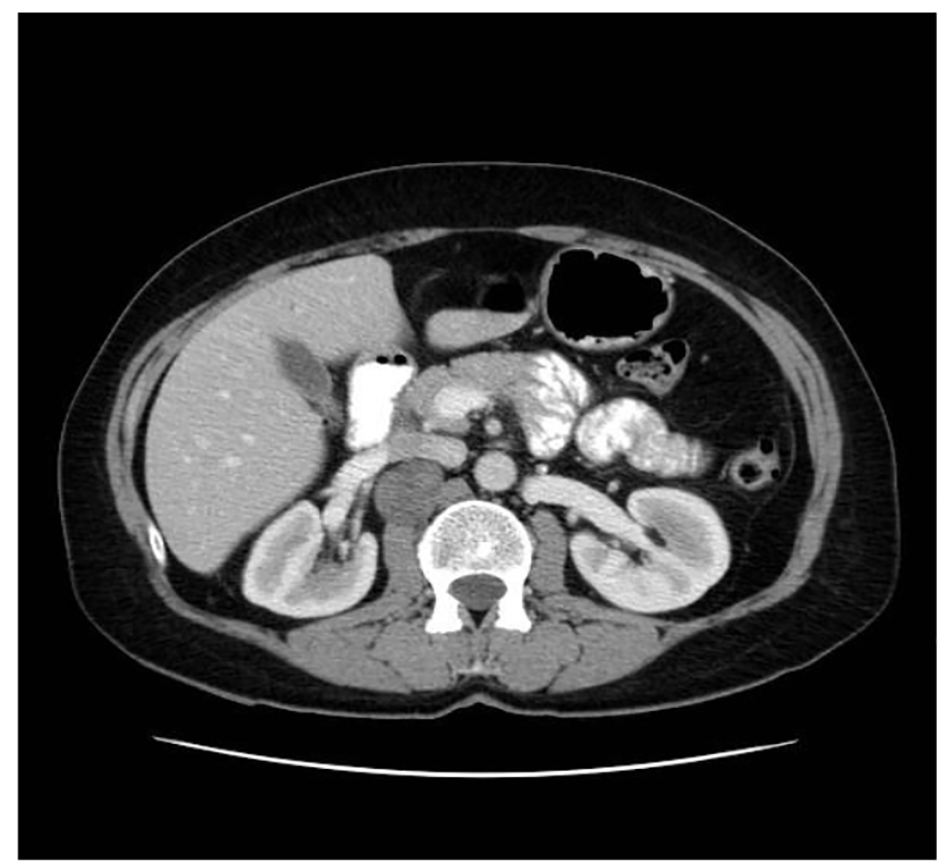

A 54-year-old female smoker presented in our department with back pain on the right. Abdominal ultrasound and CT with contrast revealed a 4.2 × 3.2 cm mass located in the retrocaval area and medial to the right kidney (Fig. 1). The findings of the images were compatible with pheochromocytoma or paraganglioma. Biochemical workup included plasma and urine catecholamine. All studies were normal. The imaging-guided biopsy was done. Microscopic findings showed a mass composed of fusiform cells with abundant collagen and spaces with macrophages. No mitoses were observed. Immunohistochemistry showed that the tumor cells were positive for S-100, BCL2, CD56, CD99 and negative for CD34 and muscle specific actin and desmin. The Ki67 activity was 1%. These findings were consistent with benign schwannoma.

![]() Click for large image | Figure 1. Abdominal CT showing a tumor occupying the retroperitoneal space. |

Because it was a benign case with small mass and the patient was asymptomatic, we decided watchful waiting with radiological periodic controls.